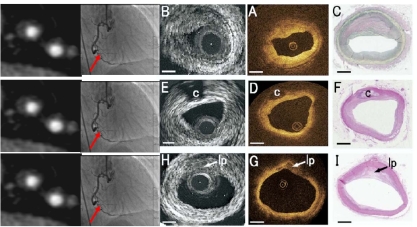

(三)冠状动脉

1. 冠状动脉粥样硬化斑块:钙化与非钙化

2. 冠状动脉管腔狭窄、闭塞

3. 冠状动脉扩张

1、冠状动脉CTA的临床价值课程的重点

1)       直接测量冠状动脉的直径判断狭窄程度;

2)       显示粥样斑块类型和部位;

3)       钙化积分的定量分析,反映病情发展,进行预测;

4)       冠状动脉支架及搭桥术后随访。